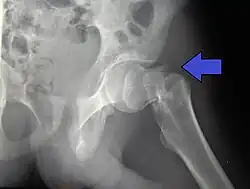

Vrijwel altijd wordt de diagnose duidelijk door een röntgenfoto. Omdat de patiëntes (of patiënten) ouder zijn en vrijwel altijd geopereerd moeten worden, zal preoperatief onderzoek gedaan worden. Er wordt bloed afgenomen, een longfoto gemaakt en een elektrocardiogram. Soms worden ook andere artsen van andere specialisaties in consult gevraagd voor medebehandeling.[1]

De collumfractuur kan volgens de Garden-classificatie worden onderverdeeld in: niet-gedislokeerd (Garden type 1 en 2) en gedislokeerd (Garden type 3 en 4).

In de meeste gevallen zal er bij een niet-gedislokeerde collumfractuur, gekozen worden voor osteosynthese. Hierbij worden de botdelen aan elkeer gezet door middel van osteosynthesemateriaal zoals de glijdende heupschroef (GHS) of gacannuleerde schroeven.

De gedislokeerde collumfractuur (Garden type 3 en 4) kan zowel worden behandeld door middel van een osteosynthese of door middel van een endoprothese. Deze keuze is afhankelijk van de leeftijd van de patiënt en de lichamelijke en geestelijke conditie. Wanneer er gekozen wordt voor een osteosynthese zal eerst de heupkop weer recht op het dijbeen gezet moeten worden, dit heet repositie. Als deze stand gelijk is aan de normale stand kan er gebruik worden gemaak van osteosynthesemateriaal. Als repositie niet of onvoldoende lukt wordt er alsnog gekozen voor een endoprothese.[1]